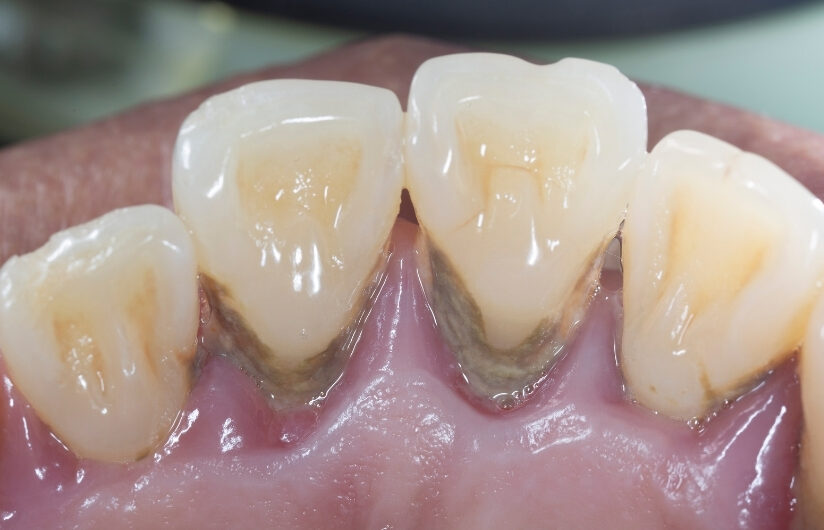

▲ 歯の表面に付着した歯石

歯の表面についた歯石やプラーク(汚れ)を取り除く処置です。

歯ぐきの外側の汚れを中心に除去するため、比較的短時間で行えます。